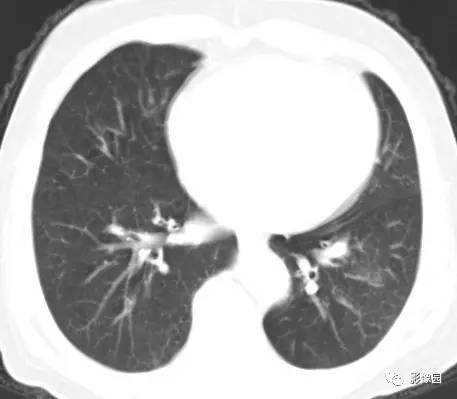

左下肺鳞癌1例CT

病史:女,77,体检发现左下肺占位5天。CT平扫肿物CT值约为40Hu,增强后约95HU 医学百科网 | YxBaike.Com

穿刺结果:(左下肺)部分肺组织:慢性支气管炎及支气管周围炎,肺泡间质纤维组织增生,个别支气管粘膜鳞状上皮化生,部分恶变,呈鳞状上皮原位癌结构,极个别区域有支气管壁早期浸润。 医学百科网 | YxBaike.Com